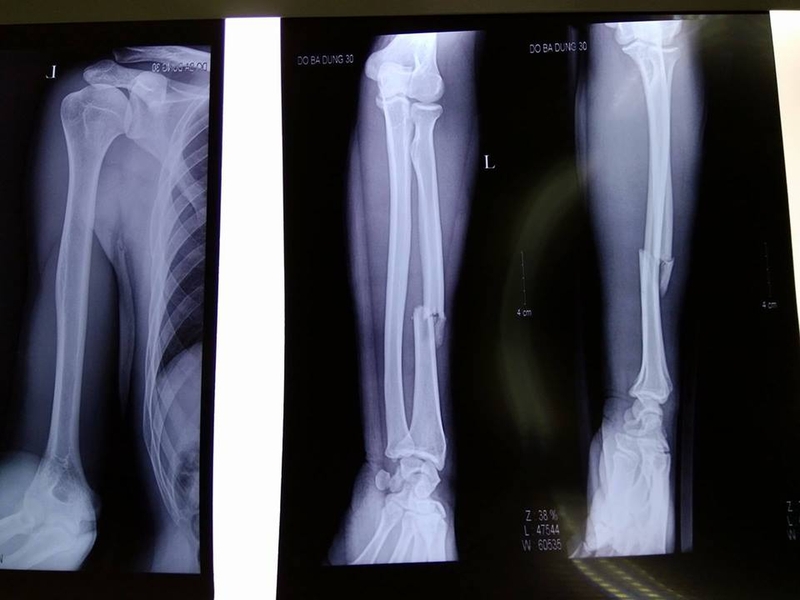

Phương pháp phổ biến nhất là chụp X-quang vùng bị thương để thấy được những biến đổi về xương, tình trạng gãy xương cụ thể, gãy xương cánh tay có nguy hiểm không. Khi thực hiện chụp X-quang, bệnh nhân cần chụp cả 2 bình diện thẳng và nghiêng để đảm bảo không bỏ sót vùng xương nào cần kiểm tra.

Chẩn đoán gãy xương cánh tay qua phương pháp X-quang